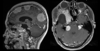

Name, characteristics, ring enhancing?

Glioblastoma multiforme

Pseudopallisading necrosis and microvascular proliferation

Ring enhancing - due to breakdown of BBB